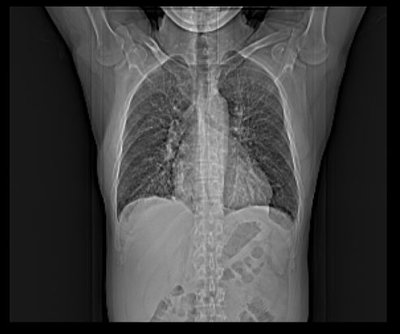

Bin nach einer Woche Krankenhaus endlich wieder zu Hause.![]()